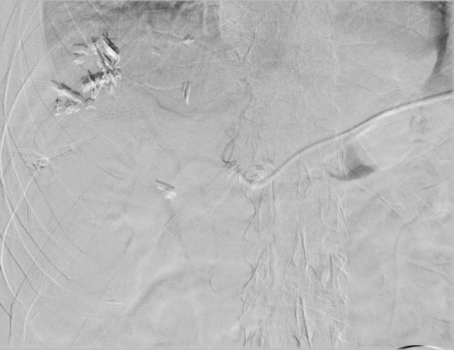

The patient notably had undergone two right thoracenteses demonstrating transudative fluid characteristics (Table 1). The patient had multiple interrogations of his hepatic artery infusion pump, including a nuclear medicine hepatic pump with SPECT/CT (Image 2) and an IR venogram (Image 3), demonstrating adequate position and functioning of the hepatic artery infusion pump with appropriate perfusion of the liver and no evidence of extrahepatic radiotracer. The patient’s labs preoperatively were all within normal limits, including normal biliary labs with AST/ALT 23/15, AP 55, and total bilirubin .3.

Image 2. IR Procedure: NUC MED HEPATIC PUMP with SPECT/CT

IMPRESSION: Appropriate perfusion of the liver after injection of radiotracer into the hepatic arterial infusion pump. No evidence of extrahepatic radiotracer collection identified.

Image 3. Procedure - IR venogram PROCEDURE: Hepatic Arterial Infusion Pump Evaluation, MAA Infusion

An angiogram was performed via the pump showing opacification of both right and left hepatic arteries. The MAA was infused. The pump was flushed with heparinized saline. The needle was removed.